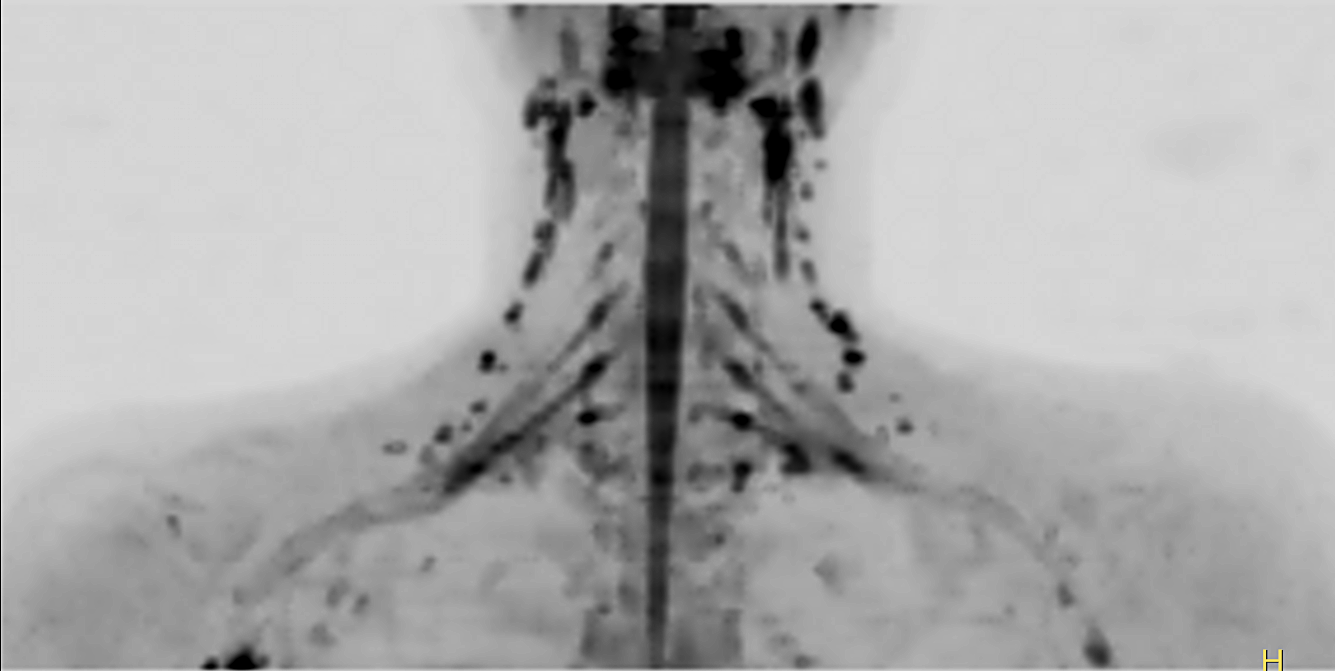

Coronal DWIBS (MIP)